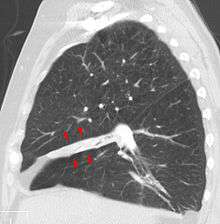

Atelectasis of the middle lobe on a sagittal CT reconstruction

Chronic atelectasis may take one of two forms—middle lobe syndrome or rounded atelectasis. In right middle lobe syndrome, the middle lobe of the right lung contracts, usually because of pressure on the bronchus from enlarged lymph glands and occasionally a tumor. The blocked, contracted lung may develop pneumonia that fails to resolve completely and leads to chronic inflammation, scarring, and bronchiectasis.

In rounded atelectasis (folded lung syndrome), an outer portion of the lung slowly collapses as a result of scarring and shrinkage of the membrane layers covering the lungs (pleura). This produces a rounded appearance on x-ray that doctors may mistake for a tumor. Rounded atelectasis is usually a complication of asbestos-induced disease of the pleura, but it may also result from other types of chronic scarring and thickening of the pleura.